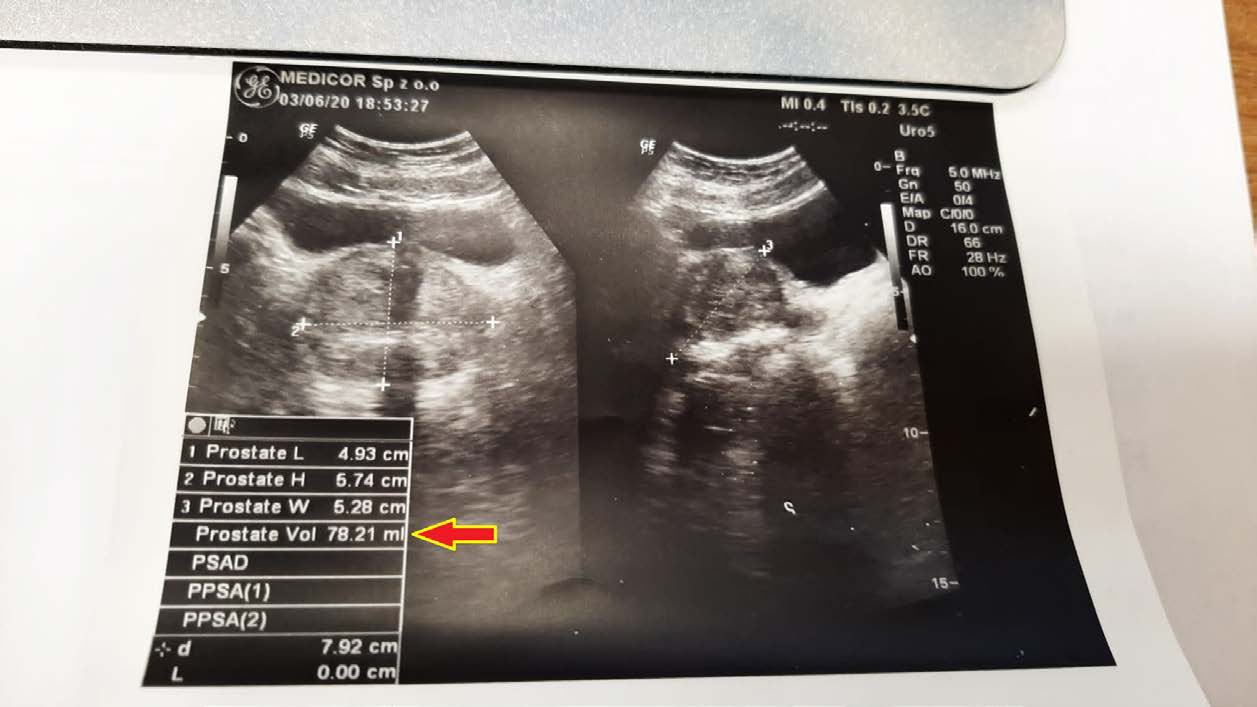

EFEKT PREPARATU NA PRZEROST GRUCZOŁU KROKOWEGO

Mężczyzna lat 50 z przerostem gruczołu krokowego, mimo iż to łagodna hiperplazja, odczuwał ból i dyskomfort przy oddawaniu moczu. Objętość gruczołu krokowego w dniu diagnozy wynosiła 78,21 ml (78,21 cm3). Po nieudanych próbach z finasterydem, podjęto próbę zmniejszenia gruczołu preparatem, jak widać ze zdjęć kontrolnych USG z sukcesem – znaczne zmniejszenie już po 2,5 miesiąca terapii do 55,97 ml (55,97 cm3).